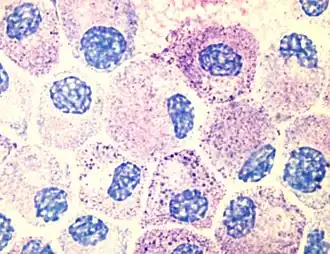

Тучные клетки. Базофильные гранулы окрашены фиолетовым

Тучные клетки присутствуют в большинстве тканей и, как правило, располагаются вблизи сосудов и нервов. Они особенно многочисленны в тканях, залегающих на границе организма с внешней или внутренней средой: коже, слизистой лёгких и пищеварительного тракта, а также в ротовой и носовой полостях и конъюнктиве[6]. В подслизистом слое слизистых, дерме, серозных оболочках, селезёнке и периваскулярной соединительной ткани тучные клетки содержатся в количестве 104—106 на 1 г ткани. На гистологических препаратах тучные клетки легко визуализируются при помощи окрашивания толуидиновым синим или алциановым синим[7]. Для тучных клеток характерен эффект метахромазии при окрашивании анилиновыми красителями из-за большого количества кислых радикалов протеогликанов[5].